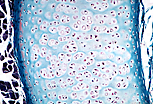

| 在明视野显微镜(MO)下, 透明软骨组织 的基质呈现无定形状态,这是因为构成基质的II型胶原纤维与基质具有相同的折射率。II型胶原纤维在常规局部染色中,仅被第三种染色剂轻微着色。 | |